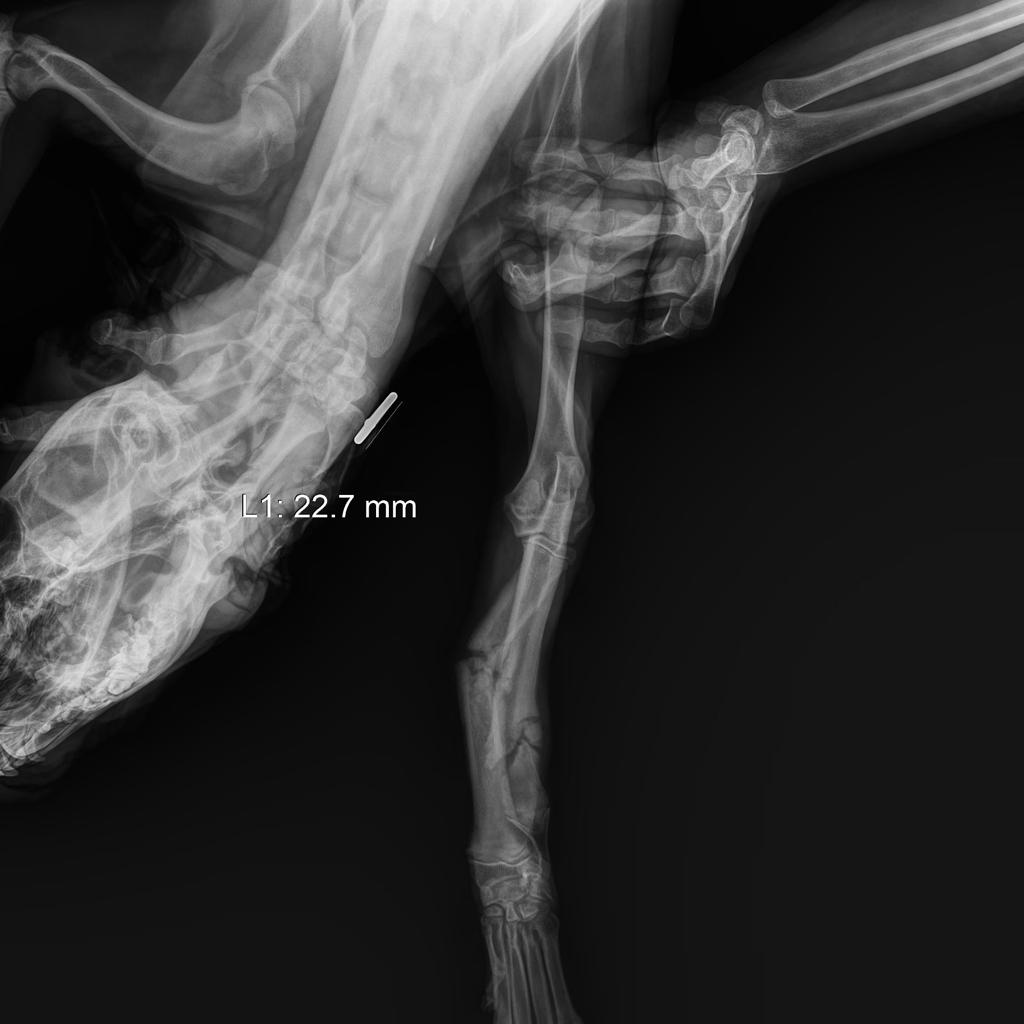

Update zu Athina! ❤️🩹

Hier sehen wir Athina auf dem Weg zum zur Tierklinik und dort angekommen, wo neben Röntgenaufnahmen des Beckens auch Ultraschallaufnahmen des Magenraums gemacht werden müssen. Es wird ersichtlich, dass hier einiges zu tun ist. Aliki musste die Hündin in der Klinik lassen und hofft nun auf positive Signale. Wir hoffen mit ihr und Athina ind bitten noch mal um Unterstützung! Jeder Euro hilft. Die Bluttests und erste kleinere Eingriffe sind abgedeckt, aber der Klinik-Aufenthalt und notwendigen Operationen reißen ein großes Loch in unser Budget? Wer hat ein Herz ♥️ und hilft uns, diese verletzte Hündin zu retten? Hilfe für Athina!

Aliki hat einen neues Notfellchen von der Autobahn gefischt. 😢

Was mit dieser armen Kreatur passiert ist, lässt sich anhand der Bilder und Videos nur erahnen, die Hinterbeine hat sie wohl wund geschliffen, da vielleicht an der Hüfte was gebrochen ist, sie insofern diese hinter sich herschleift. Das herausgerissene Stück Fell muss unsagbare Schmerzen mit sich bringen, die Arme! Wir danken Aliki, die diese junge Dame nun nicht nur erst mal zum Tierarzt gebracht hat, die ihr auch eine Schutzzone geben wird, damit diese wieder kräftiger, soweit wie möglich gesund werden kann und auch wieder Vertrauen zu Menschen gewinnen kann. Jeder Euro zählt, jede Spende, die hier eingeht, hilft! Wir drücken der Hündin die Daumen, dass sie es über die ersten Tage schafft!